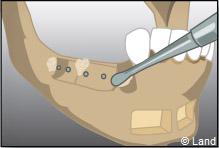

Apposition et stabilisation du greffon.

Recouvrement du greffon avec de l’os synthétique et une membrane

Apposition et stabilisation du greffon.

Recouvrement du greffon avec de l’os synthétique et une membrane